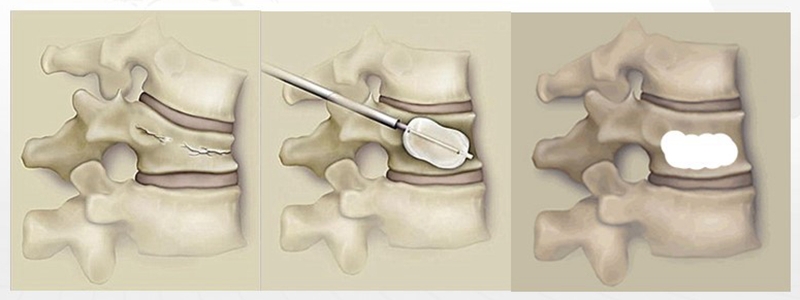

PKP的优点较PVP而言,可以有效恢复部分伤椎高度,改善后凸畸形,同时术中球囊扩张椎体后,为骨水泥灌注形成一个低压环境,减少了渗漏风险。缺点在于手术时间较PVP有所延长,同时球囊撑开椎体过程中挤压骨折界面松质骨使球囊与椎体间形成致密的松质骨壁,阻碍了骨水泥渗透入骨小梁间隙,从而增加了伤椎再骨折的可能。

PCKP的优势在于术中操作安全、便捷、骨水泥弥散好,渗漏率低。术中穿刺过程中穿刺针以更小的穿刺角度进入椎体内,通过弯角骨钻开腔越过椎体中线,增加了穿刺安全区间,减少了术中医源性穿刺损伤的风险;同时通过弯角球囊的独特设计,可以在椎体中部造成弧形空腔,引导骨水泥在灌注过程中从穿刺对侧开始弥散,沿球囊撑开的弧形空腔充分灌注,达到单侧穿刺、双侧弥散的效果,有效降低了骨水泥渗漏风险。